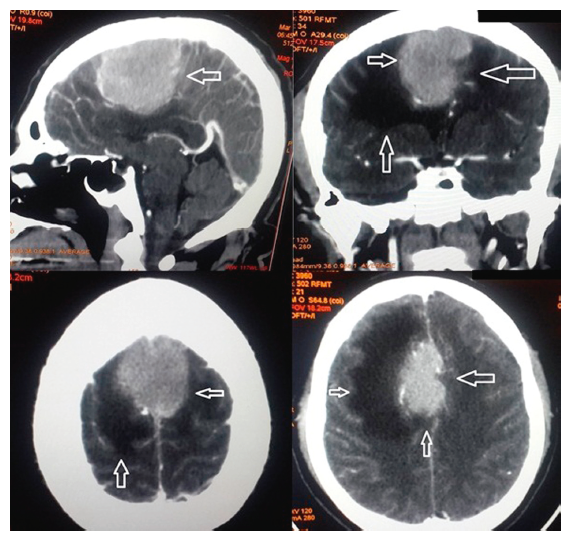

La tomografía computarizada indicó en cortes axiales imagen hiperdensa en la cisura medial, con características de meningioma dependiente de la hoz del cerebro con importante edema pericisural y borramiento del espacio subaracnoideo (fig. 1). Se ingresó con diagnósticos de: síndrome de hipertensión endocraneana, síndrome confusional agudo, edema frontal secundario y probable meningiona; iniciándose manejo con manitol, dexametasona, diclofenaco y fenitoina. El paciente presentó resolución de síndrome confusional y normalización de presión arterial. Quince días posteriores al ingreso se realizó cirugía que consistió en exceresis tumoral Simpson i intradural, con dura madre engrosada. El paciente evolucionó satisfactoriamente, con resolución de síntomas, fue dado de alta al cuarto día postoperatorio.

Figura 1 Tomografía cerebral con imagen hiperdensa en la cisura medial, con características de meningioma dependiente de la hoz del cerebro con importante edema pericisural y borramiento del espacio subaracnoideo.